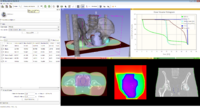

| − | Image:LobeSegmentation| Semi-automatic lobe segmentation for regional lung disease analysis as part of the Chest Imaging Platform. | + | Image:LobeSegmentation.png| Semi-automatic lobe segmentation for regional lung disease analysis as part of the Chest Imaging Platform. |

- LobeSegmentation.png

Semi-automatic lobe segmentation for regional lung disease analysis as part of the Chest Imaging Platform.

SlicerRT 0.2 has been released! SlicerRT is 3D Slicer with extensions for radiotherapy research, which is developed by SparKit project with the contributions from Slicer community.